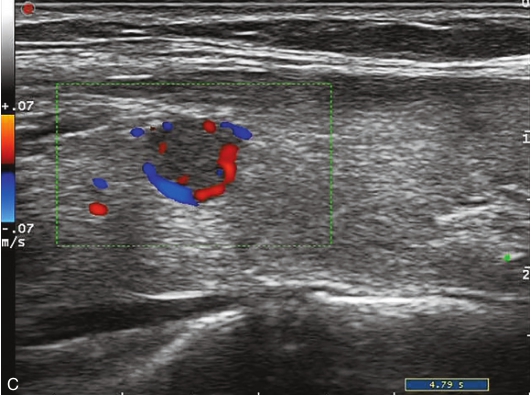

甲状腺右叶中部可见一个肿块,大小约为2.6cm×1.8cm×1.8cm,形状尚规则,边界尚清楚,内部为低回声,分布不均匀,后方回声无变化,CDFI显示肿块内可见丰富的血流信号,见图1-9-1。

图1-9-1 甲状腺髓样癌常规超声图像

A.甲状腺右叶低回声结节纵切面灰阶超声图像;B.甲状腺右叶低回声结节横切面灰阶超声图像;C.CDFI图像